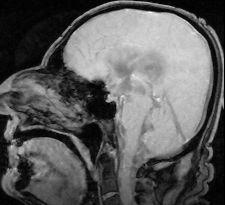

El líquido cefalorraquídeo llena las cavidades cerebrales y se encuentra tanto en el cráneo como en la propia médula espinal y actúa como un colchón entre el cráneo y el tejido nervioso . Este líquido es una solución que producen las células que se encuentran revistiendo los llamados plexos coroideos y las que revisten las superficies ventriculares, y está compuesto, entre otros elementos, de agua, sodio, potasio, calcio, cloro y sales. Una persona adulta produce a diario unos 500 mililitros de líquido cefalorraquídeo y se renueva permanentemente. Sus funciones son vitales: sirve para amortiguar golpes a fin de evitar traumas, nutre al sistema nervioso central y también sirve como cauce para los desechos metabólicos que este produzca.

«El aumento de líquido cefalorraquídeo de modo crónico, sin que llegue a producir una presión excesiva se llama hidrocefalia normopresiva. Produce una demencia insidiosa, en la que destacan desde el inicio los problemas de la marcha y la incontinencia urinaria» (González Maldonado, 2000: 116).

Líquido incoloro que ocupa el espacio subaracnoideo, los ventrículos cerebrales y el conducto central medular. Se le atribuye una función de protección mecánica, amortiguadora, del sistema nervioso central. Por otro lado, les asegura a las células del sistema nervioso unas condiciones homogéneas, adecuadas, para su actividad y actúa como sistema linfático del sistema nervioso central.